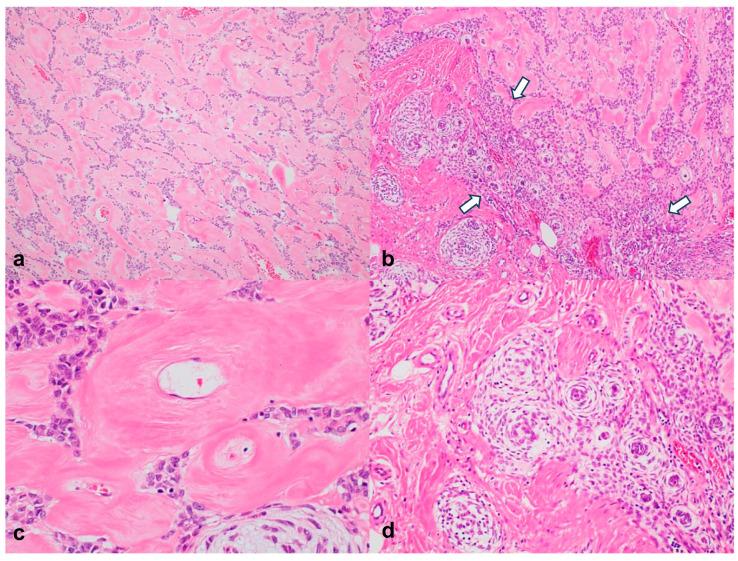

Anaplastic lymphoma kinase (ALK) is detected in both normal and oncological developmental tissues. Among ALK-related tumors, superficial ALK-rearranged myxoid spindle cell neoplasm (SAMS) is a rare, soft tissue tumor characterized by the immunophenotypical co-expression of CD34 and S100. Here, we describe a patient with this rare tumor and outline its clinical and radiological characteristics. A 28-year-old woman with diabetes, hypertension, and panic disorder presented with discomfort caused by a rubbery mass on the left buttock that had persisted for 10 years. Computed tomography revealed a multilobulated hypodense mass with small internal enhancing foci, posing challenges for the exact diagnosis of the lesion. The entire lesion was excised with clear resection margins. An 8.0 × 6.0 cm, well-circumscribed tumor with a lobular growth pattern was observed in the deep subcutaneous tissue. Light microscopy revealed epithelioid, ovoid, and spindle-shaped cells with a reticular cordlike pattern. Immunohistochemistry results were positive for S100, CD34, and vimentin. Break-apart fluorescence in situ hybridization assay results for ALK were also positive. These findings were consistent with those of SAMS. This case suggests that SAMS should be considered when identifying large nonspecific masses during clinical and imaging evaluation.

间变性淋巴瘤激酶(ALK)在正常组织和肿瘤发育组织中均有检测到。在与ALK相关的肿瘤中,浅表性ALK重排黏液样梭形细胞瘤(SAMS)是一种罕见的软组织肿瘤,其特征为CD34和S100免疫表型共表达。在此,我们描述了一名患有这种罕见肿瘤的患者,并概述了其临床和放射学特征。一名患有糖尿病、高血压和惊恐障碍的28岁女性因左侧臀部一个持续了10年的橡胶样肿块引起不适前来就诊。计算机断层扫描显示一个多叶状低密度肿块,内部有小的强化灶,这给病变的确切诊断带来了挑战。整个病变被完整切除,切缘清晰。在深部皮下组织中观察到一个8.0×6.0 cm、边界清晰、呈小叶状生长模式的肿瘤。光镜检查显示上皮样、卵圆形和梭形细胞,呈网状索状排列。免疫组化结果显示S100、CD34和波形蛋白呈阳性。ALK的断裂荧光原位杂交检测结果也为阳性。这些发现与SAMS一致。该病例提示,在临床和影像学评估中识别大的非特异性肿块时应考虑SAMS。